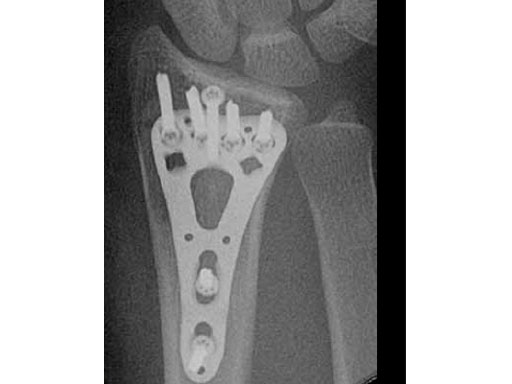

A young woman, 1,5 m tall, 45 kg, sustained a very distal C1.1 fracture of the distal radius.

Fig 3ac Postoperative x-rays showing comparison of plate alternatives.